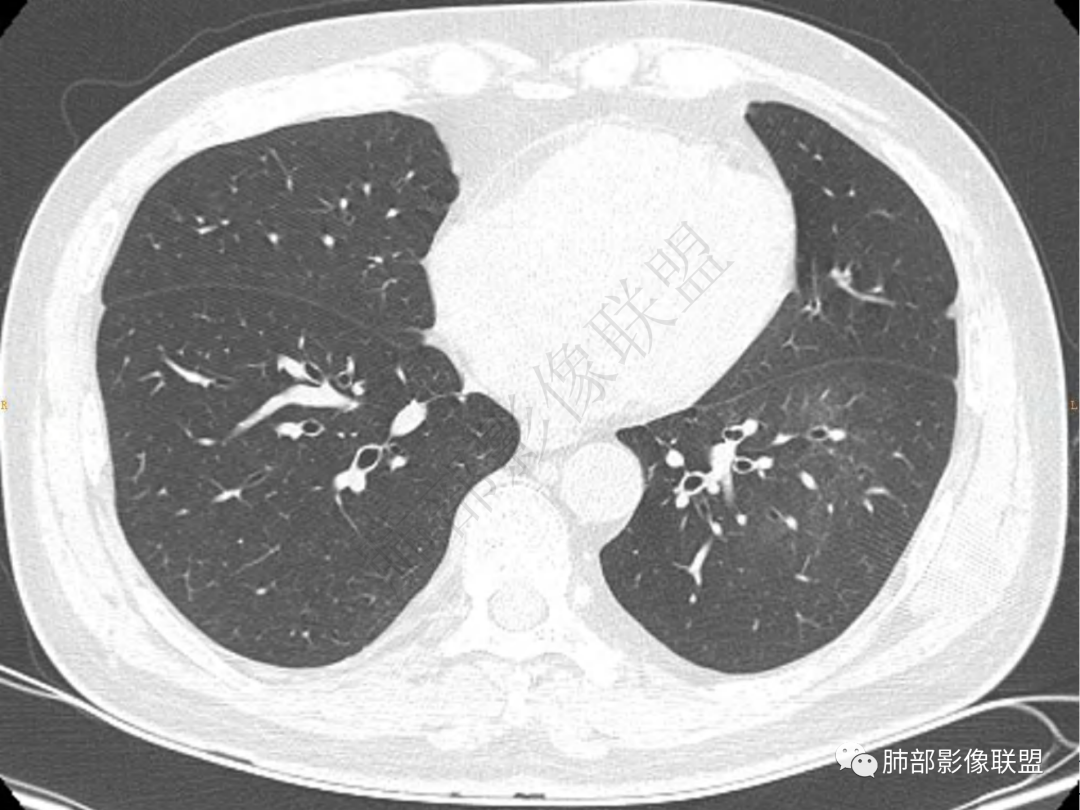

1.中年男性,咳嗽咳痰20余天,间断咯血2周

2.左肺下叶团片影,跨背段及内前基底段,实性部分类椭圆形,密度不甚均匀,可见毛刺及棘状突起,未见典型分叶及胸膜凹陷。病灶上下缘可见相应肺段支气管旁进侧出,管壁轻度增厚,未见狭窄阻塞。

3.周边较大范围磨玻璃影,边界相当模糊,小叶增厚明显。注意叶裂另一侧、左肺舌段亦可见磨玻璃影及增厚的小叶间隔。未见明确卫星病灶。

4.实性部分不均匀环形强化并显示一小范围低密度坏死区或空洞。较之肺窗,整体纵隔窗范围较小,提示病灶并不十分密实。抑或为不同时段图像。

5.双肺门及纵隔未见增大淋巴结。未见胸腔积液。